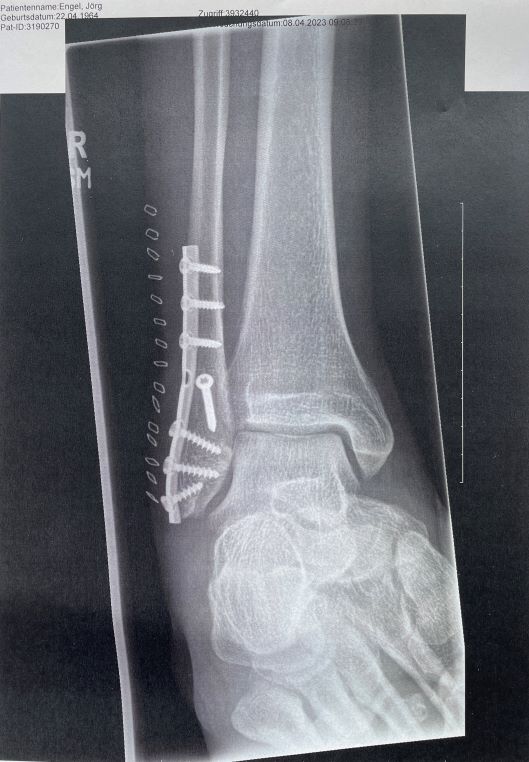

Ich brach mir die Haxe! Wadenbein Bruch. Danke!

San, Krankenhaus,(röntgen etc.) und 3 Tage später, ab ins BwK Berlin. Und das eine Woche vor Ostern.

Ka- Freitag OP und Ostersonntag wurde ich dann von einen Kamerad von meiner Staffel aus Berlin nach Hause gefahren.